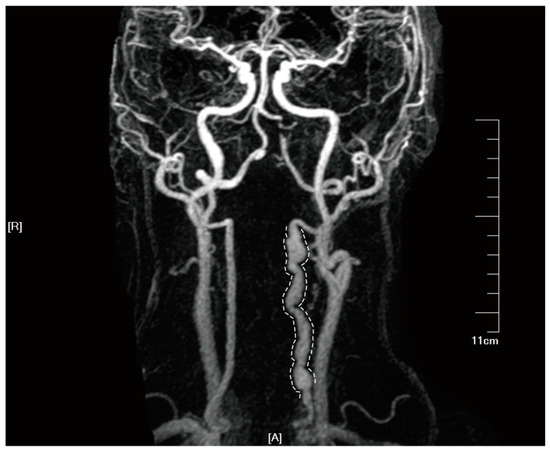

4. Imaging Characteristics of SCCAD